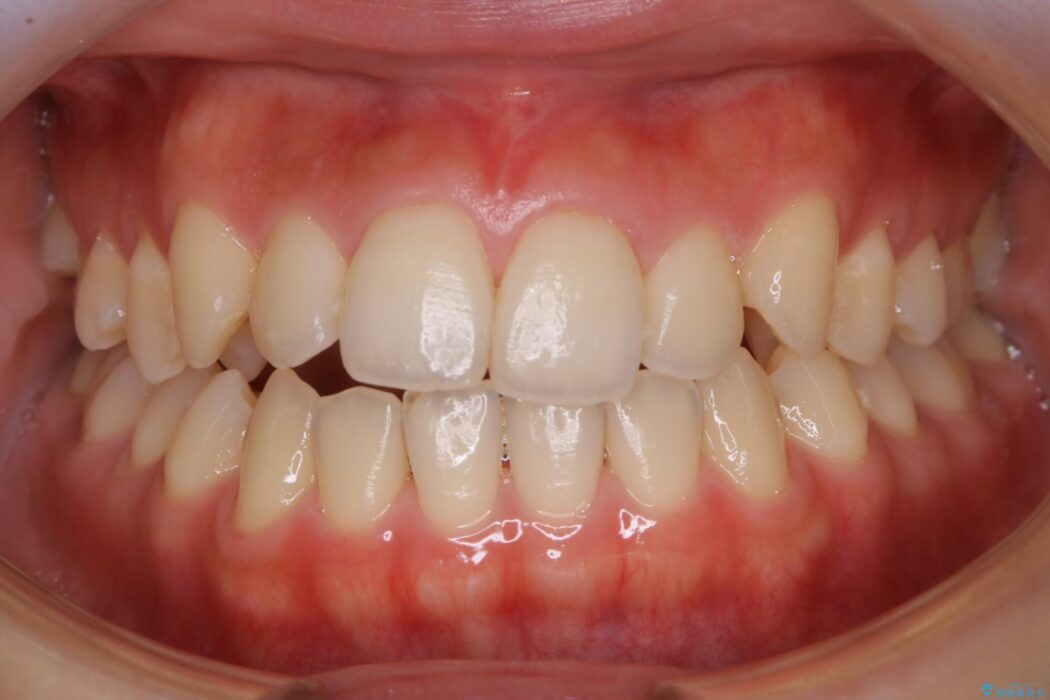

歯並びと噛み合わせが悪く治したいとの主訴で、当院の患者様からのご紹介により来院されました。

検査したところ叢生度合いから抜歯をせずとも治療が可能と判断しましたので、インビザラインでの非抜歯矯正を行う方針としました。